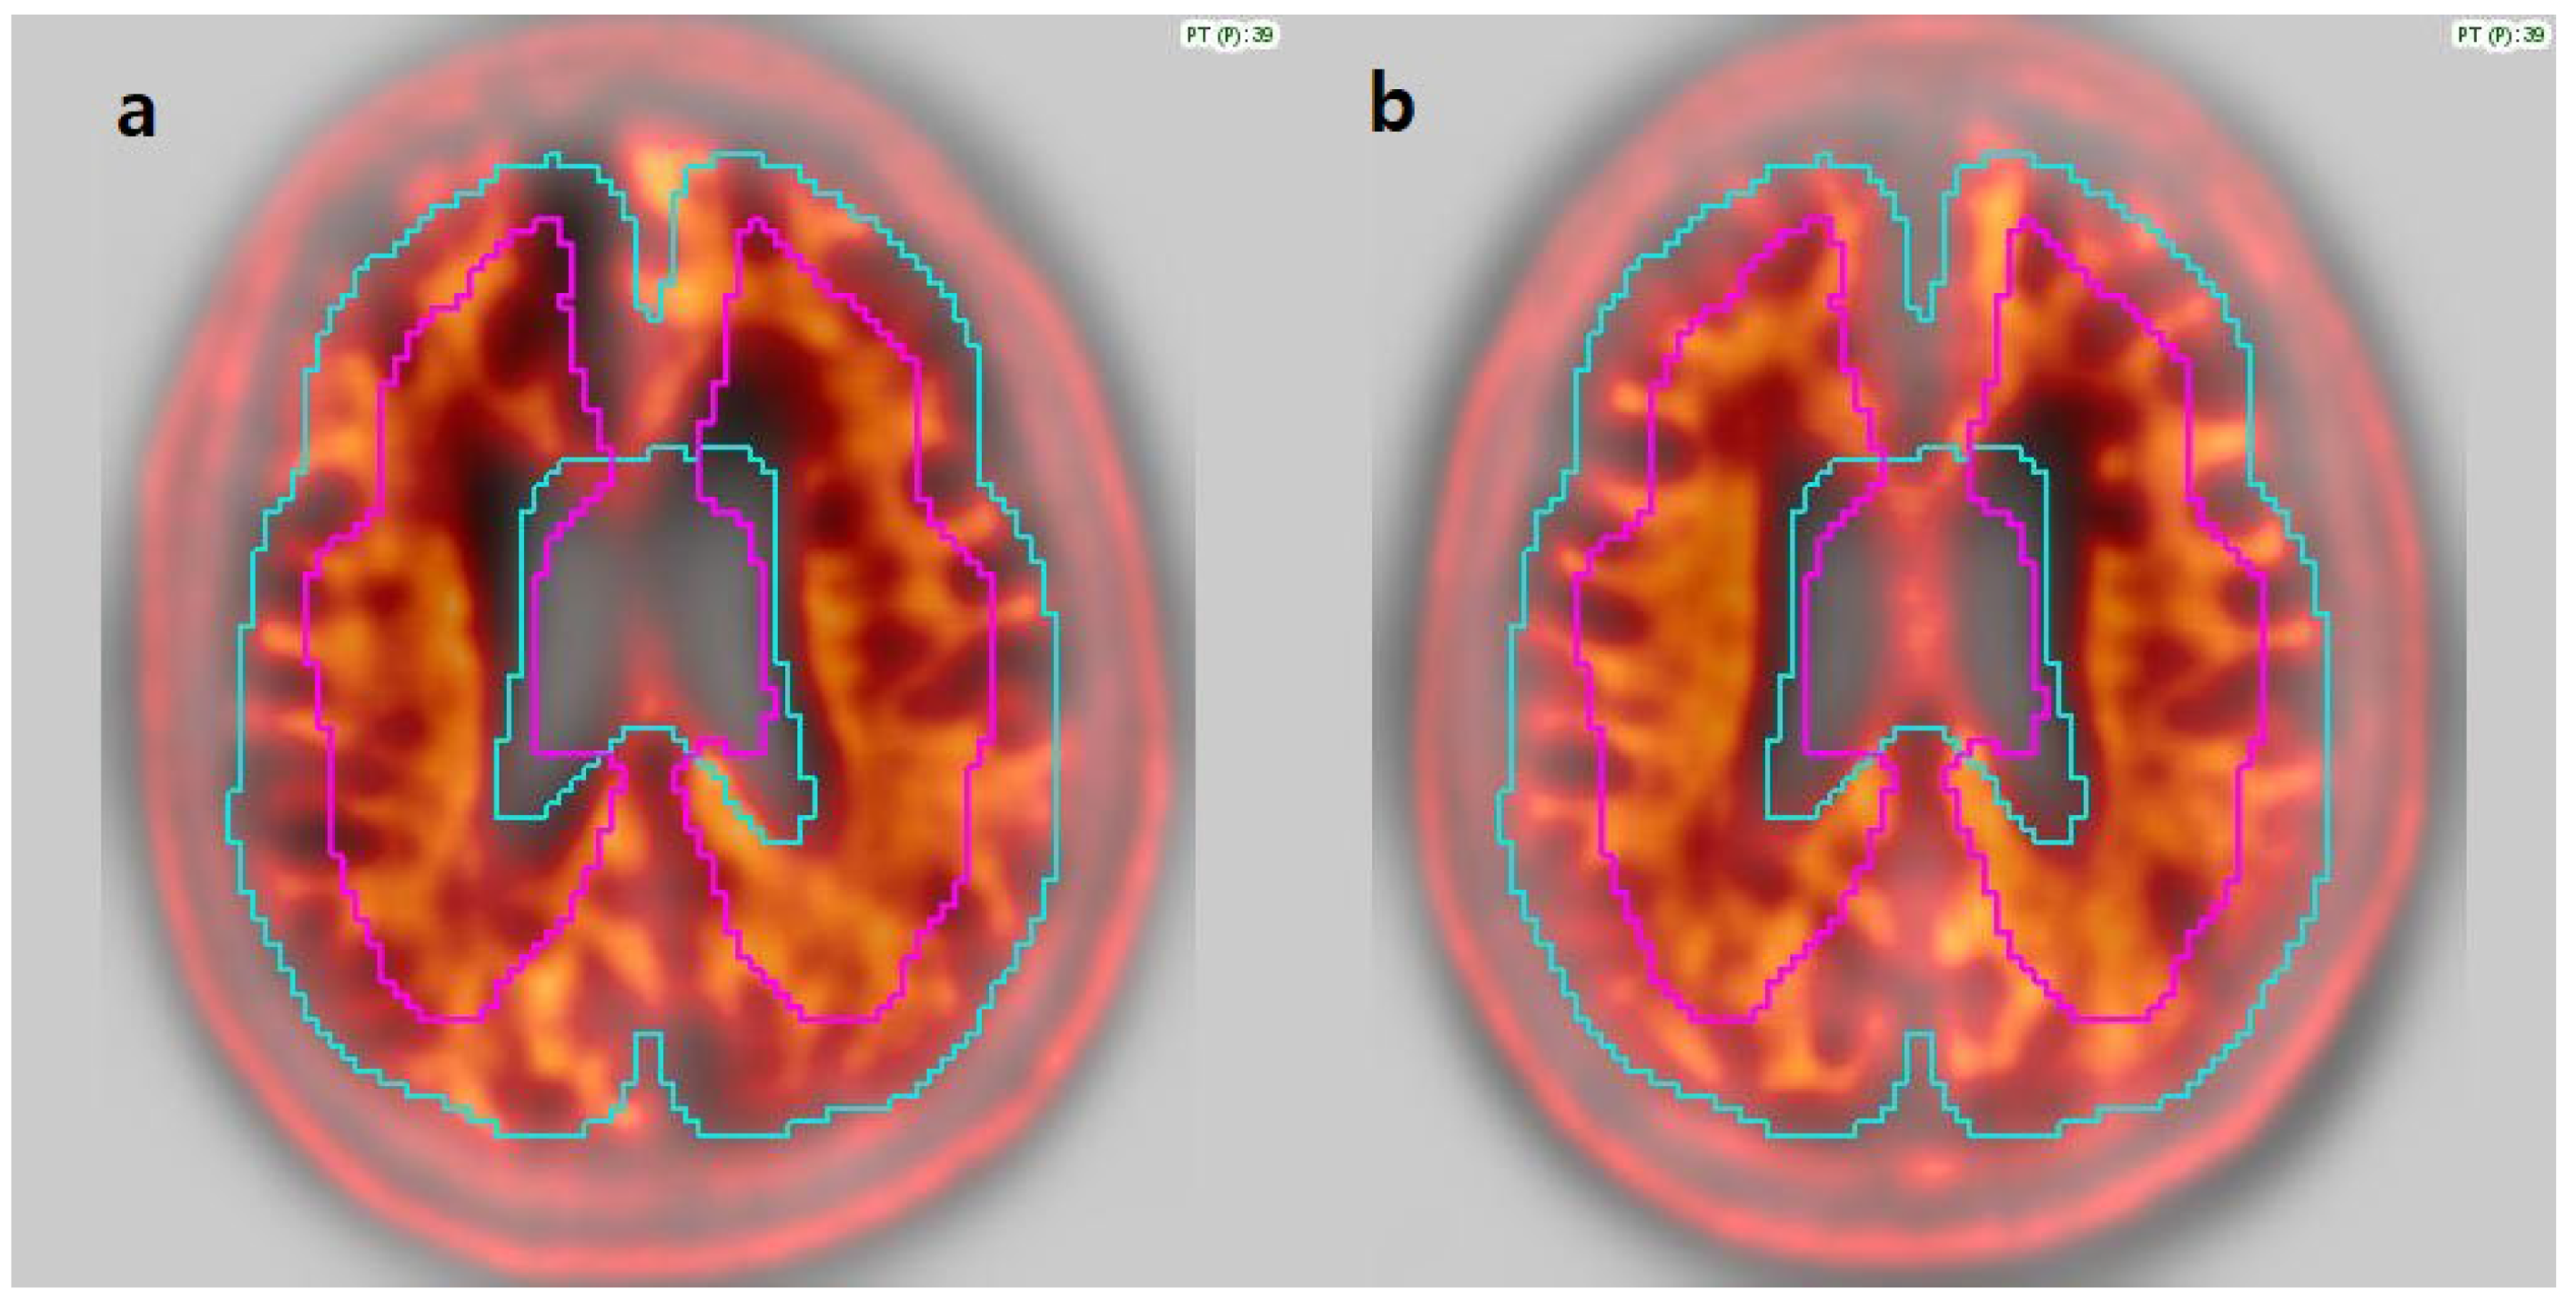

3.2. Image Analysis

3.3. Agreement Among Quantification Software